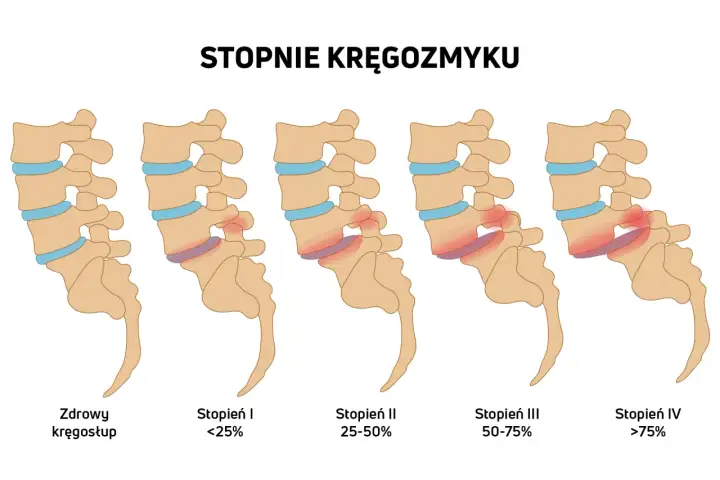

Operacja kręgozmyku - Czy to rozwiązanie dla Ciebie?

Operacja kręgozmyku: kiedy ma sens, jak wygląda kwalifikacja i powrót do sprawności? Sprawdź, czy zabieg jest dla Ciebie!